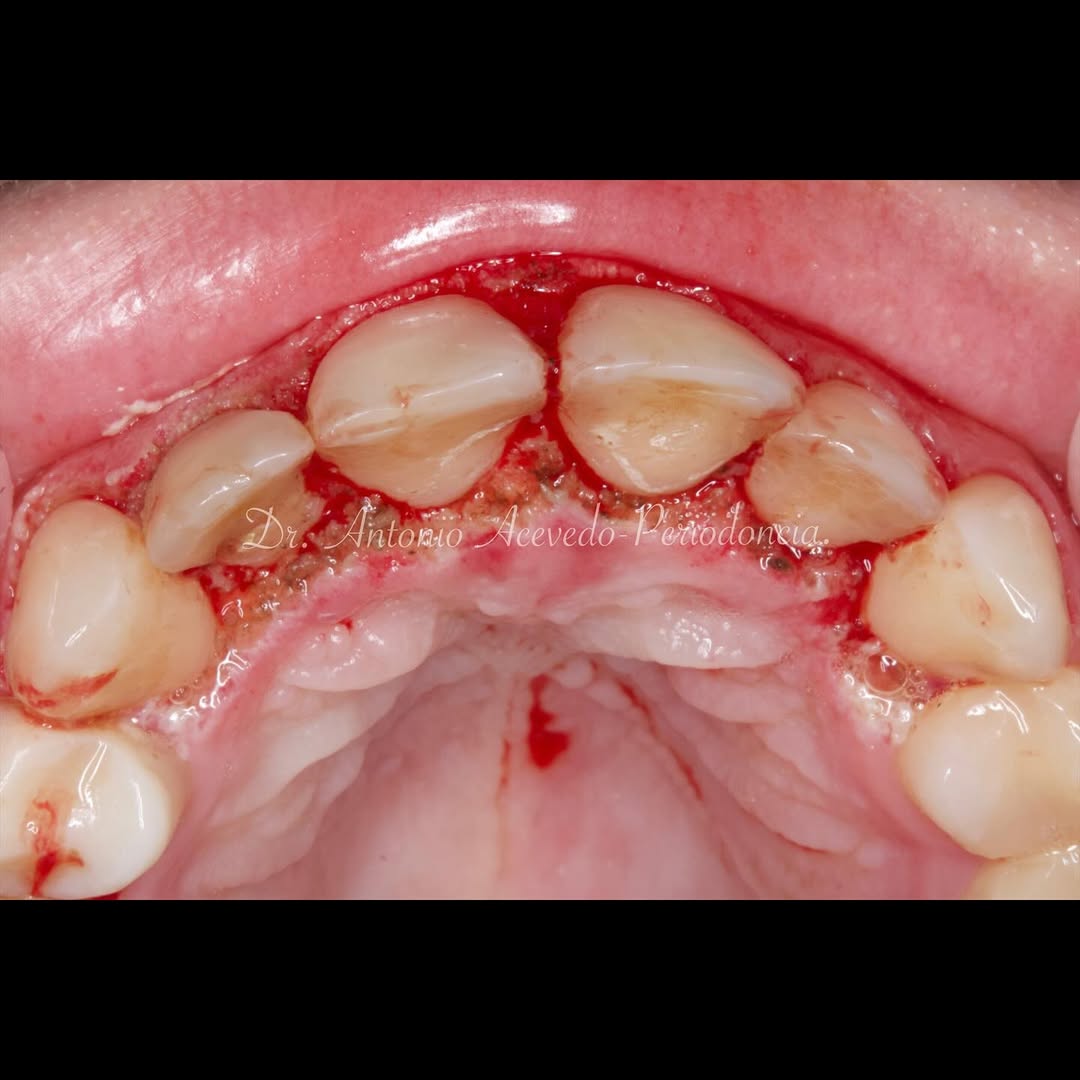

Durante una mañana, asistirás a una Cirugía Mucogingival de recubrimiento radicular de recesiones múltiples en IV y V sextante (36 a 43).

Aprende la planificación y técnica de la cirugía Mucogingival para el recubrimiento de recesiones y aumento de banda queratinizada en el sector anteroinferior